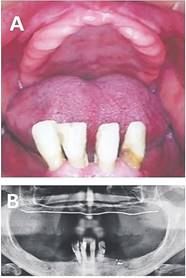

Sujeto de 67 años, ASA 1.Desdentado total superior, parcial inferior con remanencia de dientes anteroinferiores, con indicación de exodoncias por periodontitis avanzada severa y mal pronóstico protésico. Portador de prótesis total superior desajustada durante ocho años. No reporta uso de prótesis inferior. Marcada atrofia ósea alveolar y presencia de reborde móvil antero superior con superficie mucosa sana. Se planifica la confección de prótesis total superior y prótesis total inferior inmediata previa a las exodoncias. Es notificado del tratamiento a realizar, proporciona el consentimiento informado del Hospital de Carabineros de Chile, Santiago y autoriza la toma de fotografías. (Fig.1)